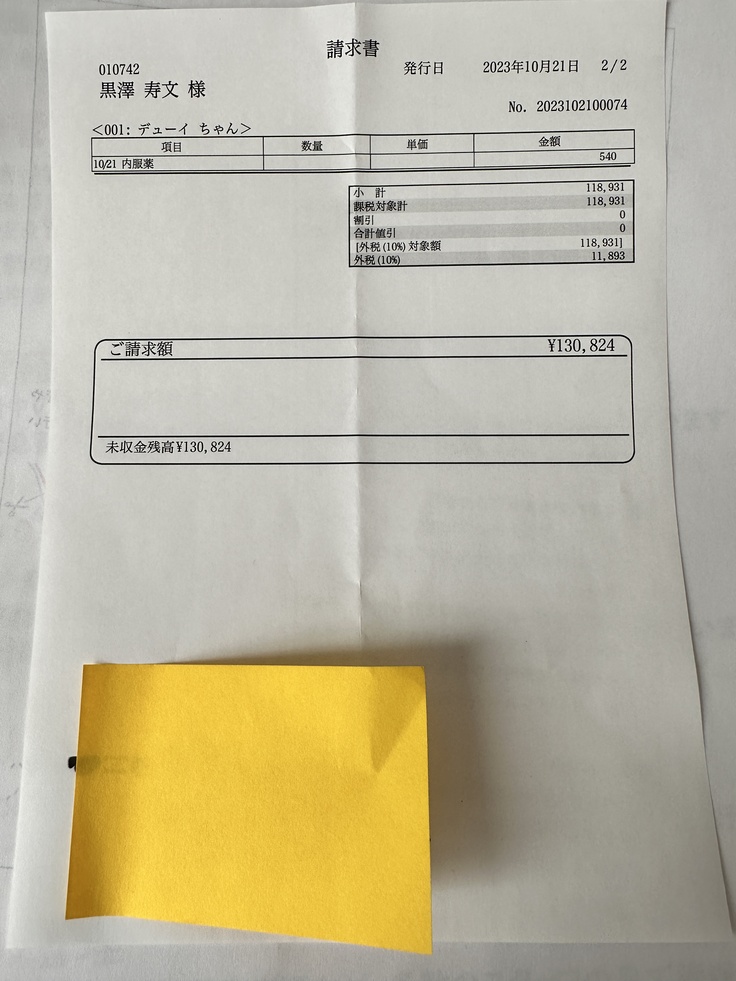

★陰唇低形成手術 (11月に手術予定)

会陰形成術を11月に予定しております。

クラウドファンディング目標金額690.000円

会陰形成手術にかかる見積もり金額

130.824円

合計 572.314円を

お願いしたいと思います。

総額690.000円とさせて頂きます。

下記は次回会陰形成手術による請求、見積もり金額となります。

会陰形成術 130.824円

愛犬デューイが二分脊椎症、骨髄膜瘤切除手術を行う。 ※手術は完了済みです。いただいたご支援は、今まで受診にあてた費用(検査、CT、MRIの費用、手術費用)441.490円のバックデート、11月に予定されている会陰形成手術費用 約130.824円として使わせて頂きます。 検査、手術費用としカードで支払ったため その引き落としが12月29日の為 上記を実施完了日といたします。